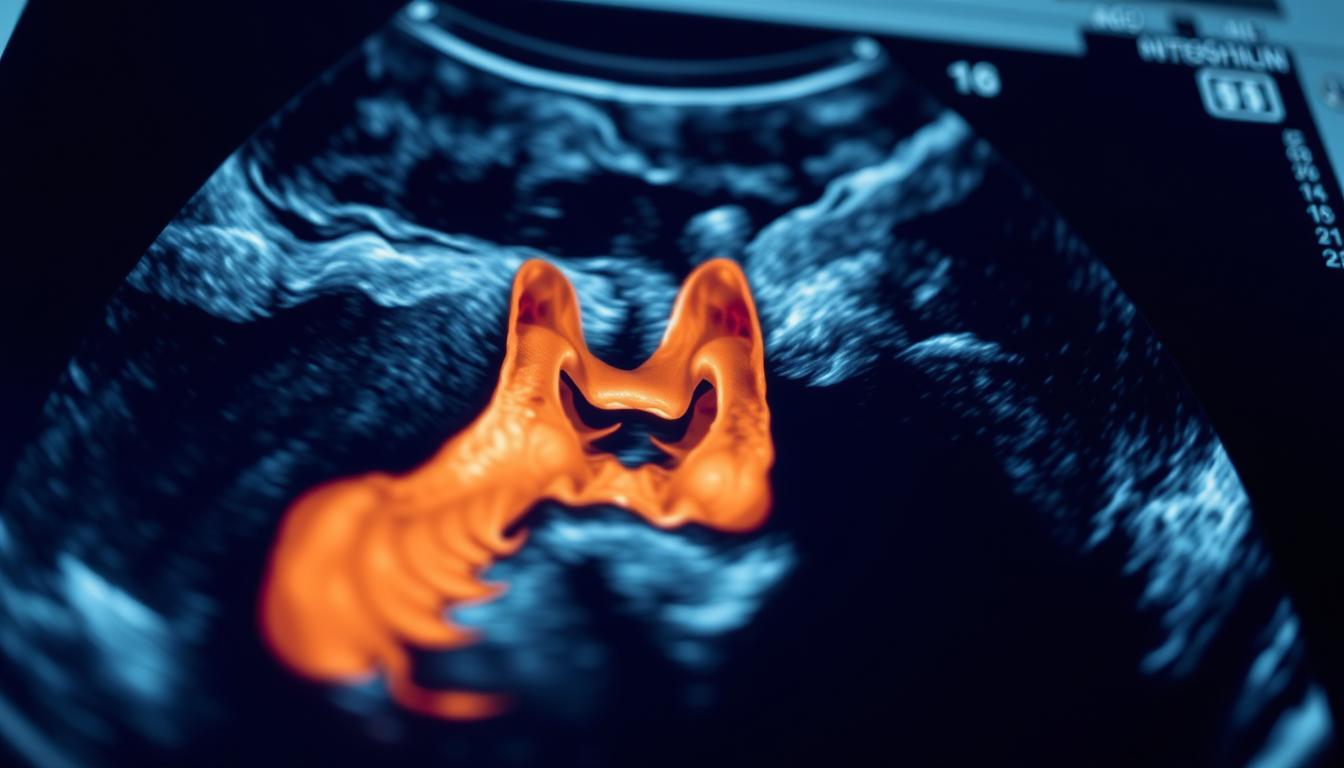

Šta pokazuju rezultati ultrazvuka štitne žlezde

Nakon obavljenog ultrazvuka štitne žlezde, rezultati mogu ukazati na različite promene u strukturi žlezde. Ultrazvuk je dijagnostička metoda koja pruža detaljan uvid u morfologiju štitne žlezde.

Normalan nalaz štitne žlezde

Normalan nalaz štitne žlezde ukazuje na to da je žlezda urednog oblika, veličine i strukture. To znači da nema vidljivih promena ili abnormalnosti.

Čvorovi (nodusi) i njihovo značenje

Čvorovi ili nodusi su česte promene koje se mogu uočiti ultrazvukom. Oni mogu biti benigni ili maligni, te je za njihovo dalje dijagnosticiranje često potrebna dodatna ispitivanja.

Ciste i druge promene u strukturi

Ciste štitne žlezde su tečnošću ispunjene šupljine koje se na ultrazvuku prikazuju kao jasno ograničene strukture. Ultrazvuk takođe može otkriti druge promene kao što su kalcifikacije i difuzne promene u ehogenosti tkiva, što može ukazivati na autoimune bolesti.

Rezultati ultrazvuka štitne žlezde se tumače u kontekstu kliničke slike i laboratorijskih nalaza hormona štitne žlezde, što omogućava lekarima da donesu tačnu dijagnozu i odrede dalji tretman.